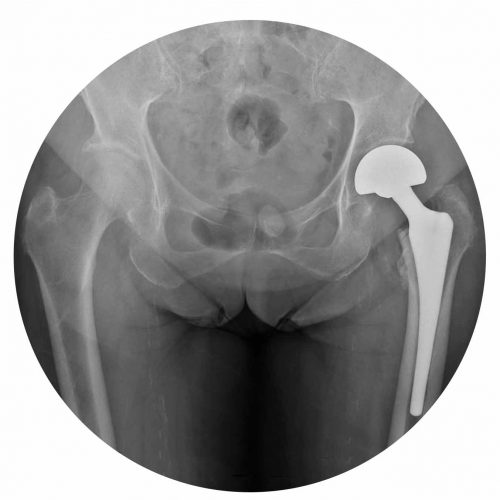

Partial Hip Arthroplasty (PHA)

Partial hip arthroplasty consists of the prosthetic replacement of the upper part of the femur and involves the placement of a stem and a metal head that articulates with the native hip socket (acetabular cavity).